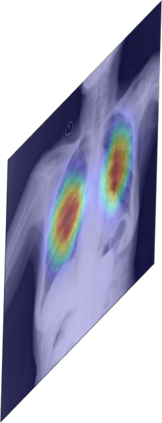

Chest X-ray (CXR) is the most typical diagnostic X-ray examination for screening various thoracic diseases. Automatically localizing lesions from CXR is promising for alleviating radiologists' reading burden. However, CXR datasets are often with massive image-level annotations and scarce lesion-level annotations, and more often, without annotations. Thus far, unifying different supervision granularities to develop thoracic disease detection algorithms has not been comprehensively addressed. In this paper, we present OXnet, the first deep omni-supervised thoracic disease detection network to our best knowledge that uses as much available supervision as possible for CXR diagnosis. We first introduce supervised learning via a one-stage detection model. Then, we inject a global classification head to the detection model and propose dual attention alignment to guide the global gradient to the local detection branch, which enables learning lesion detection from image-level annotations. We also impose intra-class compactness and inter-class separability with global prototype alignment to further enhance the global information learning. Moreover, we leverage a soft focal loss to distill the soft pseudo-labels of unlabeled data generated by a teacher model. Extensive experiments on a large-scale chest X-ray dataset show the proposed OXnet outperforms competitive methods with significant margins. Further, we investigate omni-supervision under various annotation granularities and corroborate OXnet is a promising choice to mitigate the plight of annotation shortage for medical image diagnosis.